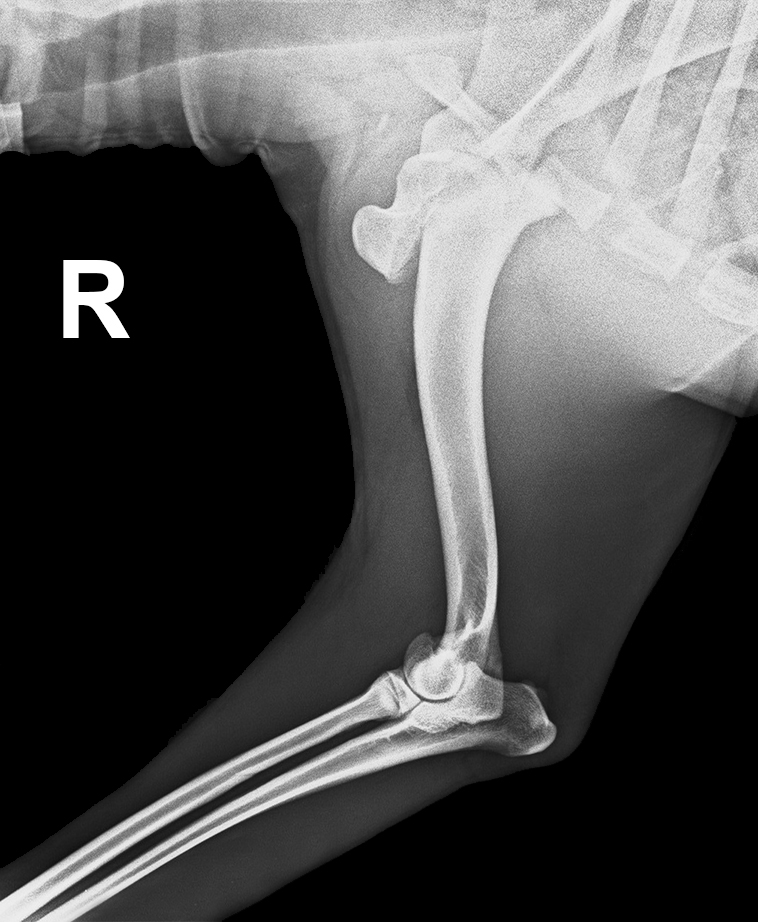

ARTROVET Fractura en cara medial del epicóndilo del húmero en gato

ARTROVET Fractura del proceso medial del cóndilo humeral

ARTROVET Fractura de la fisis proximal del húmero